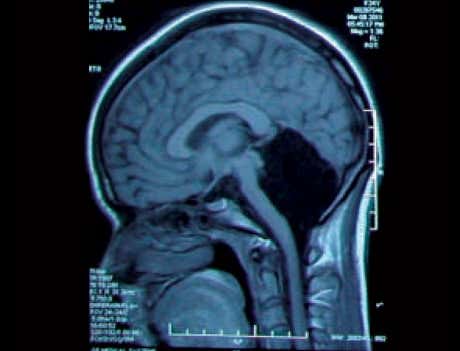

Случай, который попал в журнал The Lancet в 2007 году, дал исследователям богатую пищу для размышлений. В статье речь шла о французе, который потерял 90% головного мозга. Мужчине на момент проведения исследования исполнилось 44 года, и он даже не подозревал, что с ним что-то не так. Он обратился к медикам с жалобами на слабость в правой ноге, и ему, в рамках общего обследования, назначили сканирование мозга. Врачи, которые рассматривали снимок, сначала подумали, что аппарат неисправен. Голова мужчины на 90% была заполнена жидкостью. От мозга остался лишь тонкий слой по периметру черепа, а центр полностью отсутствовал. Несмотря на такой фатальный недостаток тканей мозга, мужчина имел низкий, но приемлемый уровень интеллекта — 75 баллов. При этом он вёл нормальный образ жизни: работал в государственной конторе, вместе с женой растил двоих детей. Если бы не слабость в ноге, он бы и не узнал о «пустоте» в голове.

Врачи предположили, что мозг пациента в течение 30 лет медленно разрушала гидроцефалия, поэтому он и не заметил изменений. При гидроцефалии, или водянке головного мозга, в тканях накапливается огромное количество жидкости, которая не адсорбируется в кровоток, а постепенно «разъедает» мозг. Диагноз мужчине поставили во младенчестве, после чего врачи на 14 лет имплантировали стент для расширения артерии и отвода жидкости. Но в подростковом возрасте каркас сняли. С тех пор жидкость опять начала накапливаться, постепенно разрушая мозг.

Точный диагноз французу поставили только в 2017 году. Потеря почти всего мозга случилась из-за прогрессирования хронической не сообщающейся гидроцефалии, из-за которой жидкость накапливалась очень медленно. И 90% мозга не отсутствовало, как думали медики. Скорее всего, ткани мозга под давлением сильно сжались, и остался лишь тонкий слой по периметру подкорки.